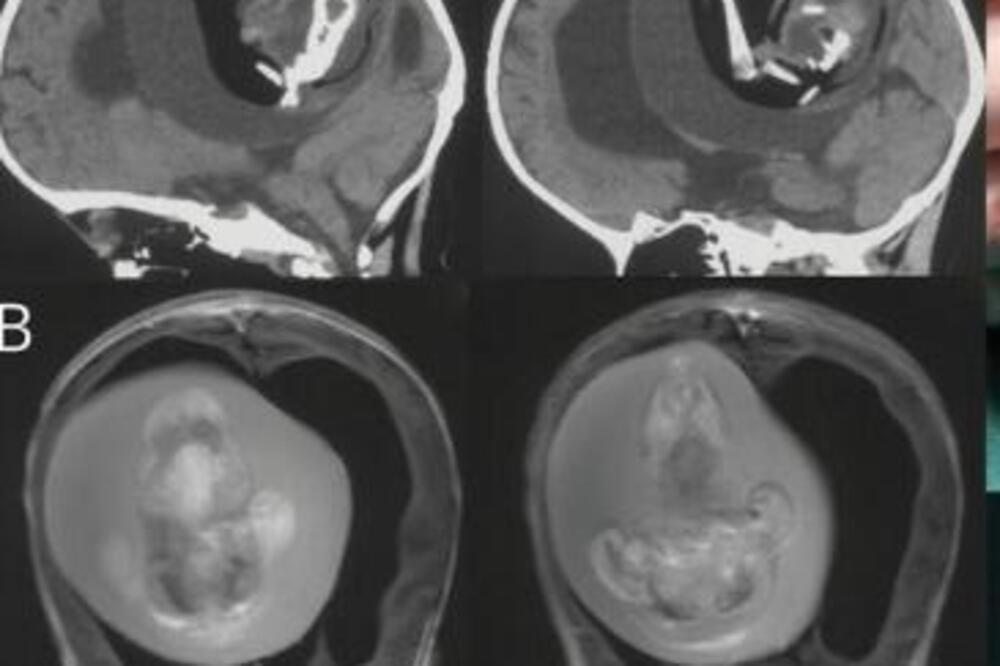

Devojčica iz Šangaja u Kini imala je tek godinu dana kada su roditelji primetili da njihova ćerka ima slabe motoričke funkcije, ali i da joj se glava nesrezmerno uvećava u odnosu na telo. Zbog toga su otišli u bolnicu, doktori su uradili skener i zaprepastili se. U mozgu devojčice razvijao se novi fetus!

"Intraventrikularni fetus u fetusu, odnosno deformisani monohorionski dijamnionski blizanac, identifikovan je kod jednogodišnje devojčice sa motoričkim kašnjenjem i uvećanim obimom glave", navodi se u studiji objavljenoj u časopisu "Neurology" u decembru prošle godine. Pojednostavljeno, sestra blizankinja rasla je u mozgu ove jednogodišnje devojčice.

Nakon hirurškog uklanjanja, sekvenciranje celog genoma otkrilo je identične varijante sa jednim nukleotidom kod deteta domaćina i 'fetusa u fetusu', kako su doktori i zaključili da je fetus zapravo bio 'nerođeni blizanac'.

"Spojeni delovi se razvijaju u prednji mozak fetusa domaćina i obavijaju drugi embrion tokom savijanja neuralne ploče", navodi se u studiji.